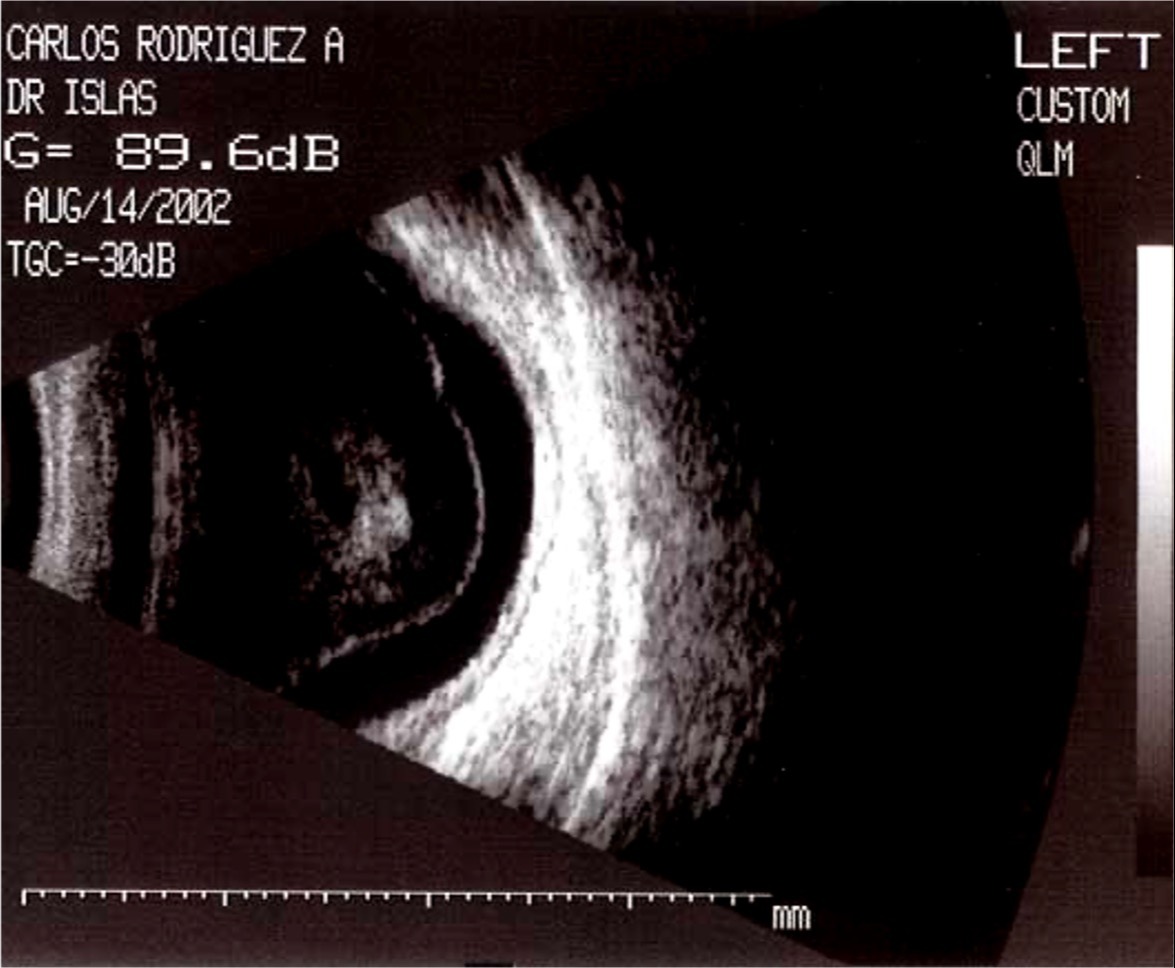

Sospecha de desprendimiento de retina traccional (DRT).

Evaluación preoperatoria en casos de vitrectomía.

Control postquirúrgico de cavidad vítrea.

Valoración de masas intraoculares o fibrosis proliferativa avanzada.